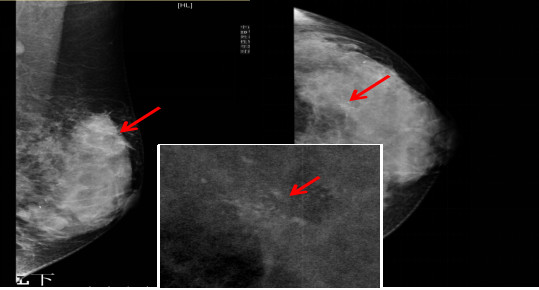

乳腺钼靶:左乳外上象限肿物,伴“簇状钙化”。BIRADS分类:4类。